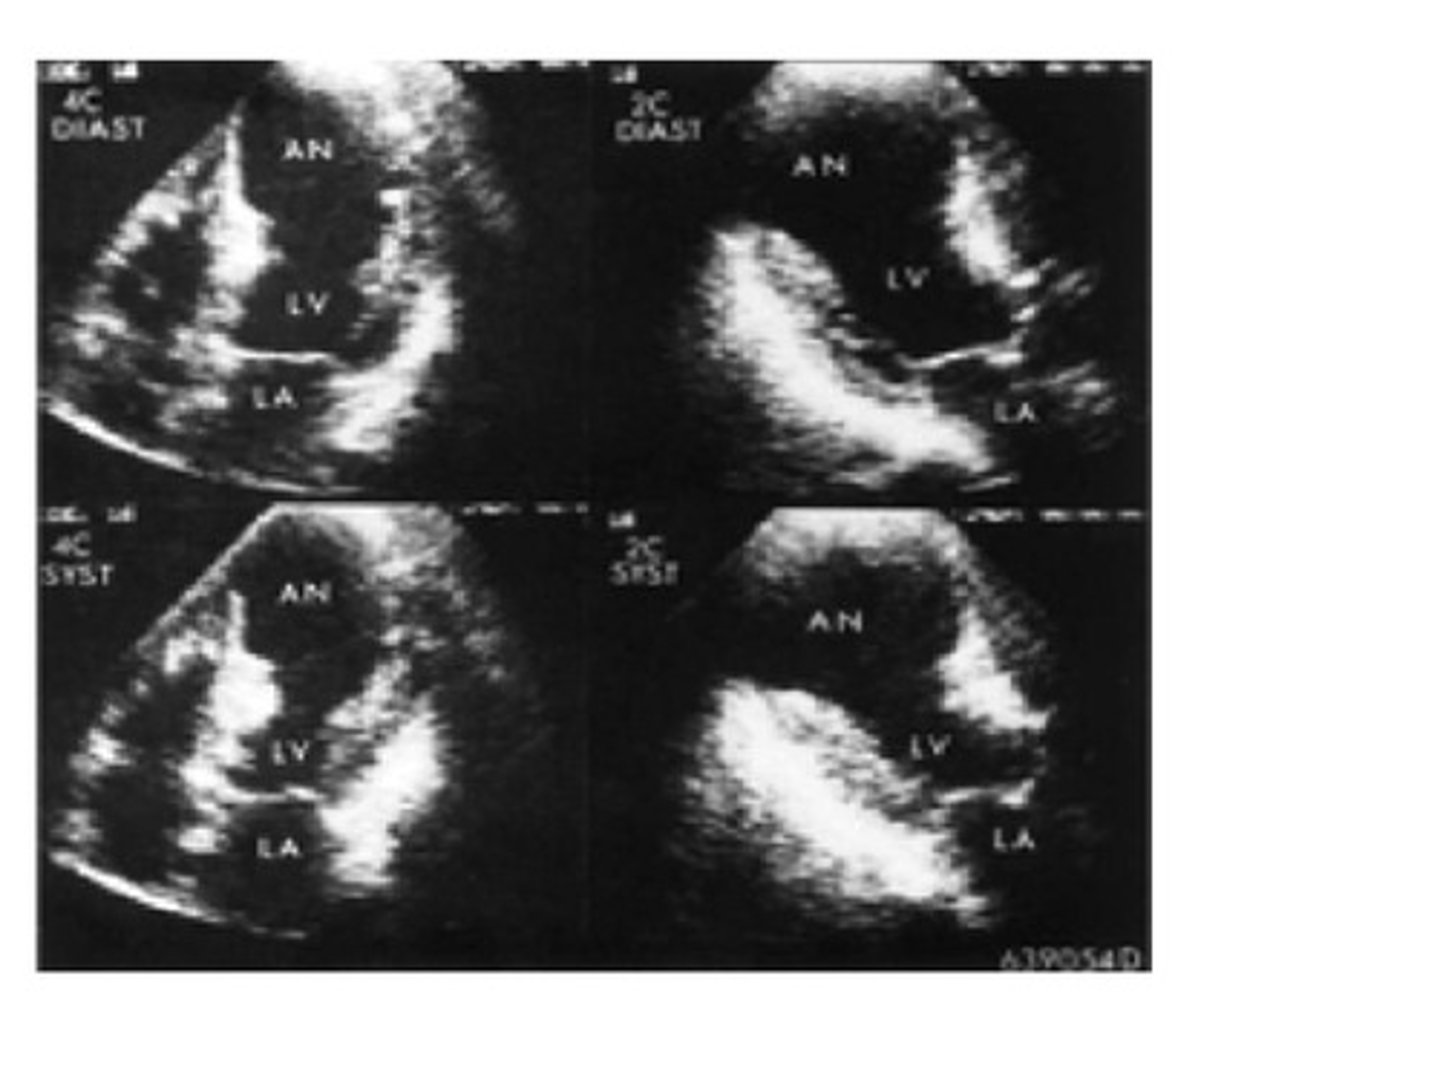

Reviewing the image, the left ventricle has a bulge in the apex which could have been caused by a myocardial infarction. The bulge in the apex is known as:

thrombus

aneurysm

clot

stenosis

A bulge in the left ventricle along with the thinning of necrotic tissue of the infarcted wall and the high pressure in the ventricle during ejection may cause which of the following?

rupture

regurgitation

nothing is at risk of happening